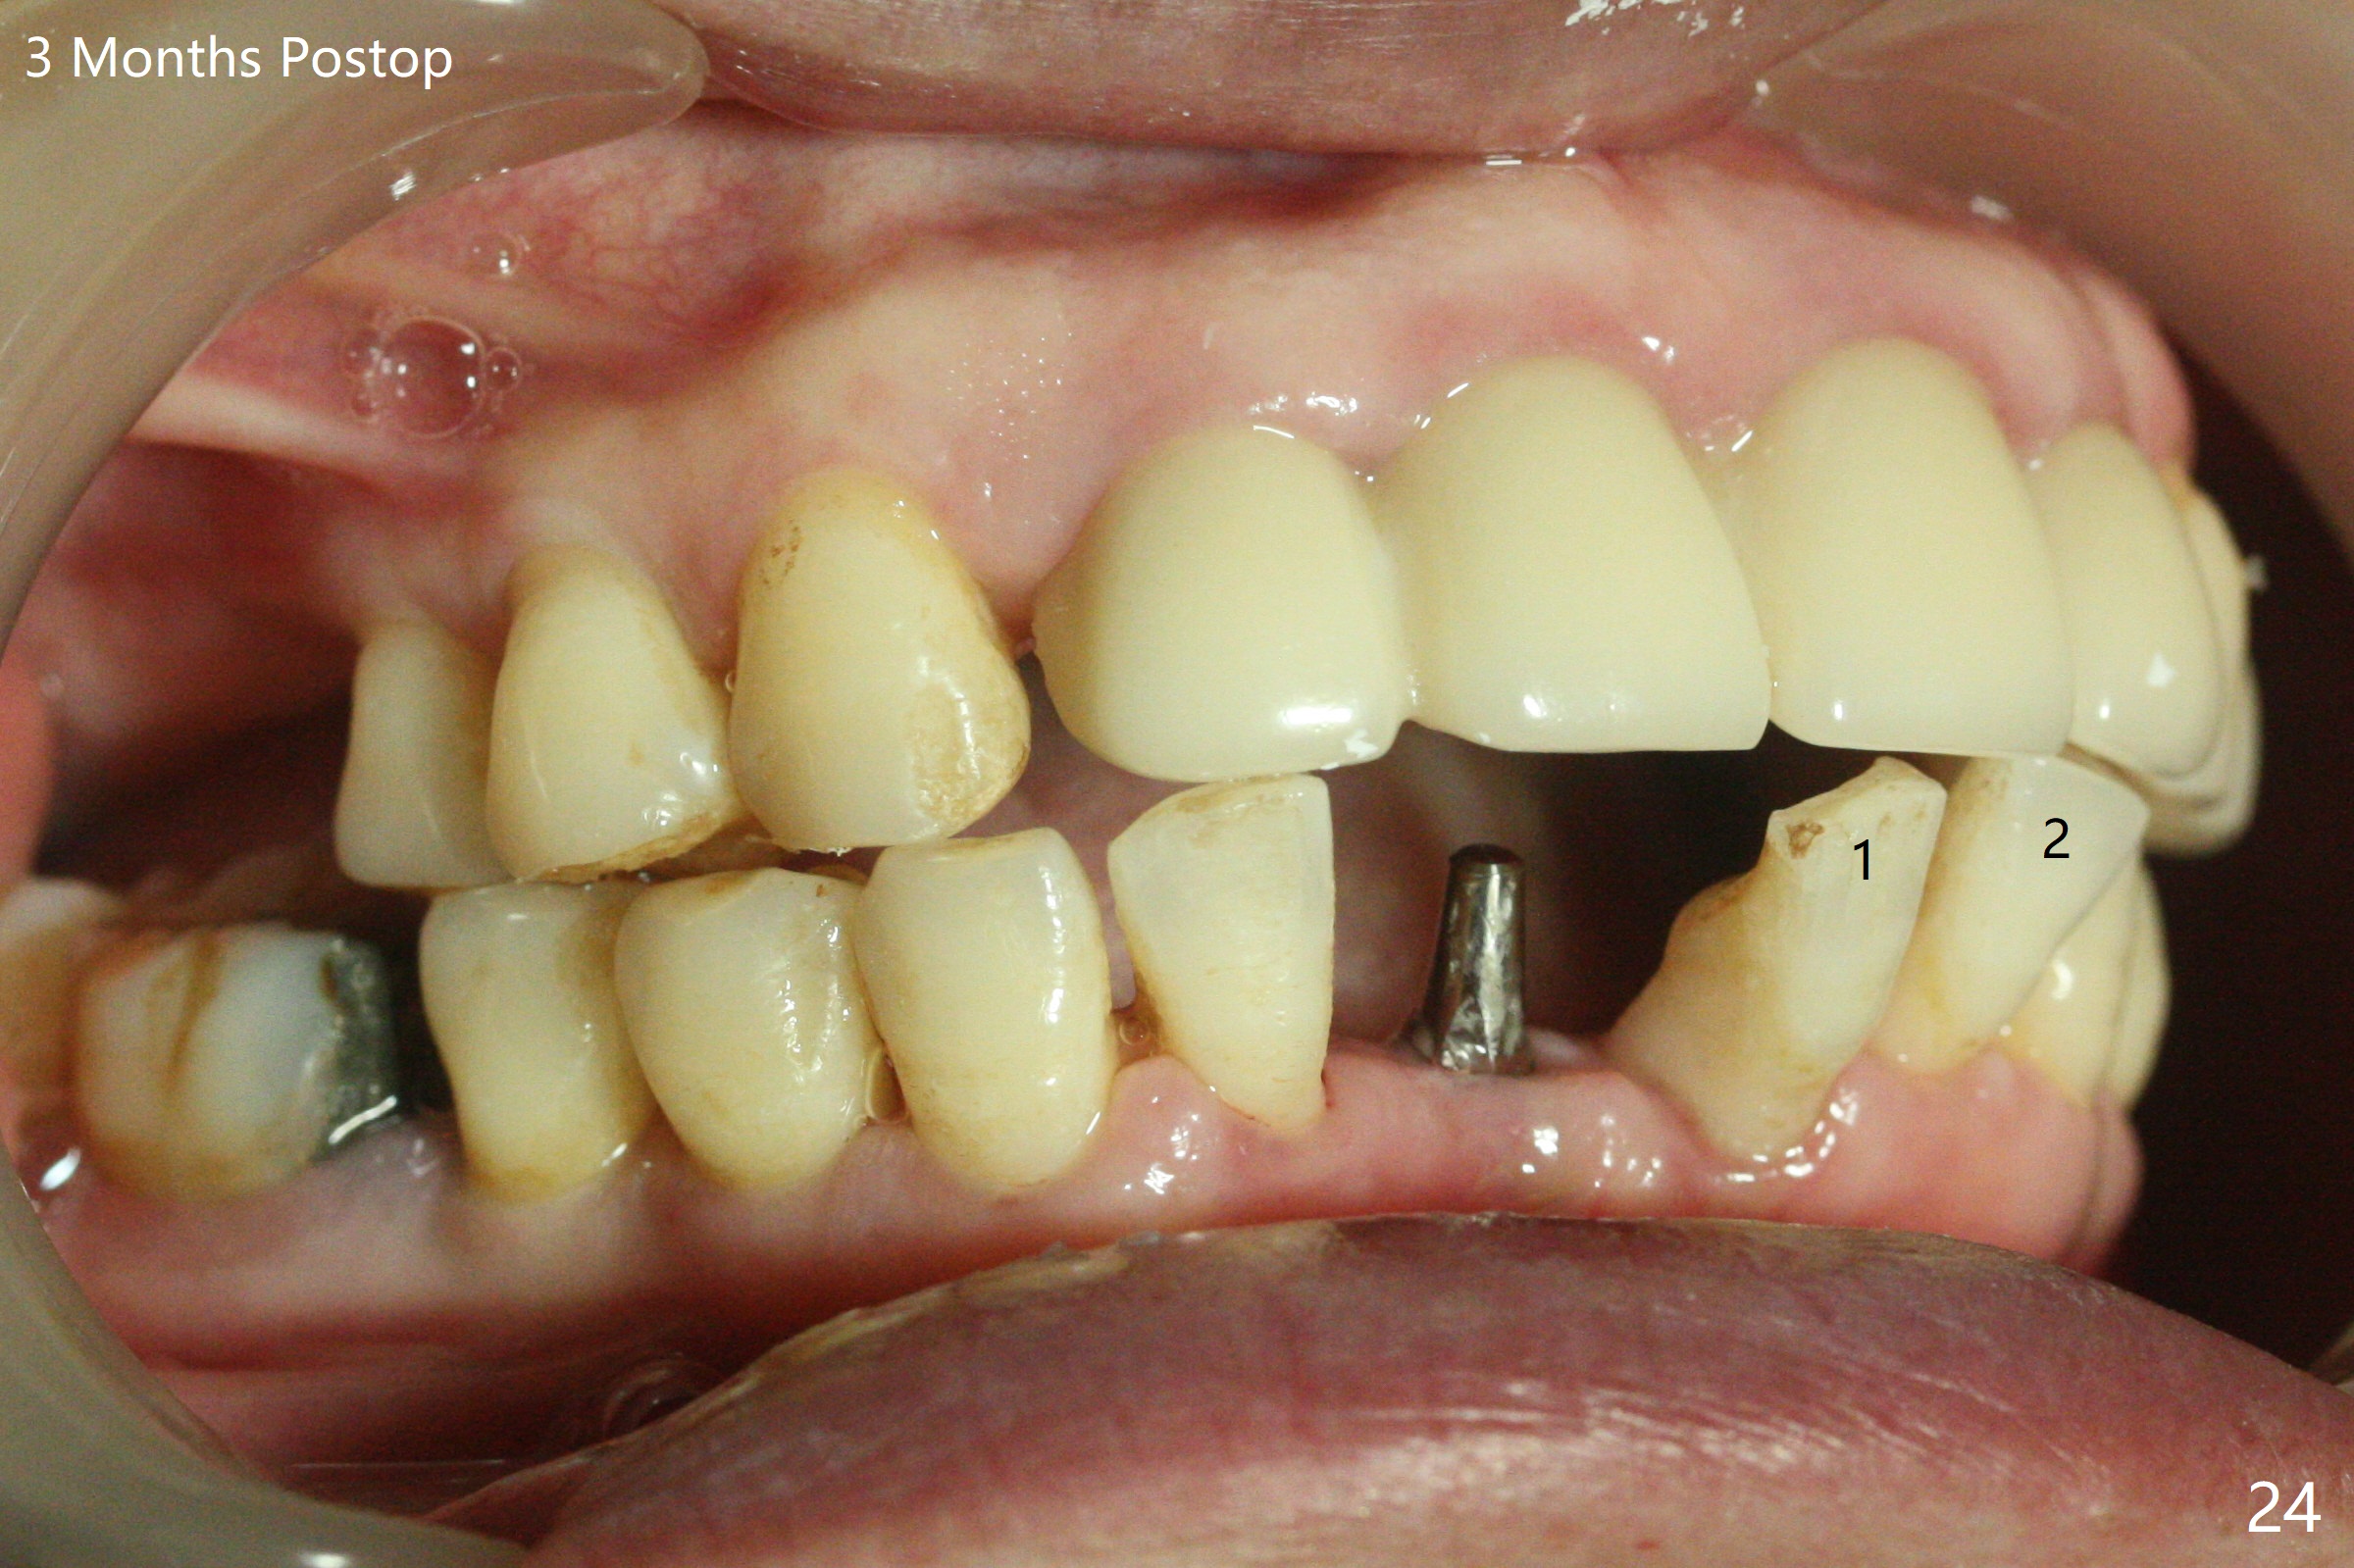

56岁女十分恐惧治疗,缺失右下1,其余切牙由于骨质吸收颊侧移位(图一:1,2),但是她不愿意拔除,同意右下1种植,牙周骨手术,植骨;植体整合后作为支抗,矫正移位下门牙。为了防止忘记舌侧瓣分离,先做舌侧切口(图二),然后颊侧瓣松弛分离(图三),包括使用前牙隧道刀(图四)切断颊侧骨膜,松弛到颊侧瓣能向舌侧牵拉3-4毫米(图五),舌侧瓣骨膜下广泛,深部分离(好像不能切断骨膜,图六),放置导板,磨平狭窄的牙槽嵴(图七:O(osteotomy)),植入2.5x12(4)毫米一段式植体(图八:故意舌侧植入,以便以后矫正),在颊侧骨板打多个出血洞(图八:箭头),然后把在平的器皿上形成的粘性骨板(sticky bone,图九),放置于植体和移位切牙周围(图十),接着使用消毒过的橡皮障punch(图十一(纸头相当于PRF膜;事先给助手示范))在三个PRF膜(图十二)打洞,套在植体和门牙上(图十三: 箭头),防止膜(图十四)和骨块(图十五,十六:*)移位,最后还必须使用最原始方法牙周敷料保护伤口(图十七)。术后9天,舌侧牙周敷料脱落,伤口稍微裂开(图十八)。术后18天撤除敷料,伤口裂开处有新鲜肉芽组织生长(图十九(*:下面是填入的骨粉,将是增宽的牙槽嵴(如果你是乐观主义者)),二十)。病人十分感激我们帮助她度过难关。她的确有sleep apnea,否定tongue thrust。术后三个月植体周围没有明显骨质吸收(图二十一至二十三),左下1,2轻度反合(图二十四),植体周围软组织健康(图二十五),5-5安置矫正器(图二十六,二十七,12 niti)。一周后下切牙向舌侧移动(图二十八),左下1,2反合纠正(图二十九)。再一周变化不大(图三十),植牙圈有些松动,两周后将重做临时牙冠,槽往舌侧移动。结果病人提前回来,植牙槽舌侧移位。一周后右下2不适(图三十一),尝试近中牵引(图三十二)。